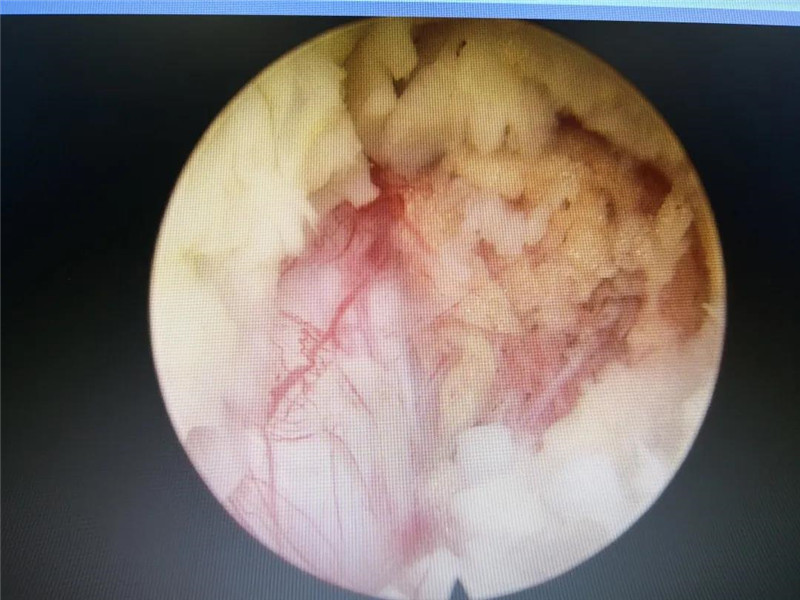

潘磊主任专注手术中 术中Delta******

术中患者腰部神经清晰显露